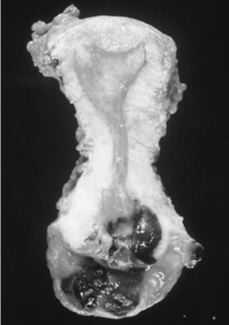

Con el diagnóstico anatomo-patológico de melanoma maligno de vagina y cérvix se realiza tratamiento quirúrgico radical: vulvectomía (incluyendo las lesiones del tercio inferior de la pared vaginal posterior, con márgenes macroscópicamente libres), histerectomía con doble anexectomía vía vaginal (incluyendo las lesiones del tercio superior de la pared vaginal anterior), linfadenectomía inguinal y pélvica bilateral (Fig. 1).

Figura 1.Corte longitudinal del útero. Melanoma invadiendo cérvix uterino.